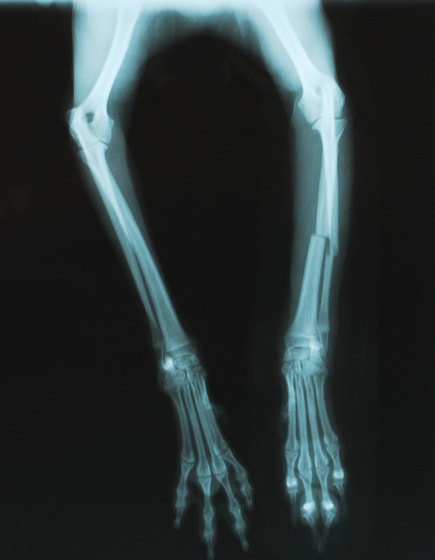

症例3:キルシュナーワイヤーのピンニングによる整復

ペルシャ猫 11ヶ月齢 雄

他院にて左大腿骨遠位の成長板骨折(salter-harrisⅠ型)が認められており、治療相談を目的として来院。当院にて、キルシュナーワイヤーを用いたピンニングにより骨折部位の整復を行いました。術後の経過は良好で、現在も経過観察中です。

術前レントゲン

術後レントゲン